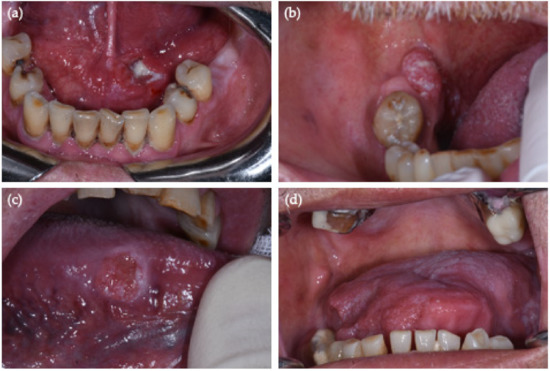

| OSCC Site (By New NIH/SEER ICD-0-3.2 System) | No. (%, 95% CI) | No. HPV-Positive OSCC (%, 95% CI) | Sex/Age | PCR HPV-DNA | p16 IHC |

|---|---|---|---|---|---|

| Border of tongue (C02.1) | 13 (32.5%, 95% CI = [19–49%]) | 2 (15%, 95% CI = [2–45%]) | M/65 | HR-HPV 31 + 68 | − |

| M/65 | HR-HPV 66 | − | |||

| Overlapping lesions of tongue/no base of tongue (C02.8 = C02.1 + C02.2) | 4 (10%, 95% CI = [3–24%]) | 0 | − | − | − |

| Gum (C03.1) | 2 (5%, 95% CI = [0.6–17%]) | 0 | − | − | − |

| Anterior floor of mouth (C04.0) | 4 (10%, 95% CI = [3–24%]) | 1 (25%, 95% CI = [0.6–80%]) | M/44 | HR-HPV 51 | + |

| Hard palate (C05.0) | 3 (7.5%, 95% CI = [2–20%]) | 0 | − | − | − |

| Buccal mucosa (C06.0) | 7 (17.5%, 95% CI = [7–33%]) | 0 | − | − | − |

| Retromolar area (C06.2) | 7 (17.5%, 95% CI = [7–33%]) | 1 (14%, 95% CI = [0.3–58%]) | M/61 | HR-HPV 67 | + |